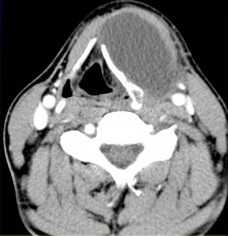

(Слева) КТ с КУ, аксиальная проекция. Образование овальной формы в заднемедиальном отделе сонного пространства. Обратите внимание, что сонная артерия находится на передней поверхности опухоли, а внутренняя яремная вена - на латеральной. Незначительное накопление контраста не очень характерно для шванном, в данном случае вид опухоли напоминает нейрофиброму.

(Справа) MPT Т2ВИ, аксиальная проекция. Округлое образование с неоднородным сигналом, которое смещает общую сонную артерию кпереди. Внутренняя яремная вена смещена вместе с артерией. При сдавливании яремной вены ее идентификация может быть затруднена.